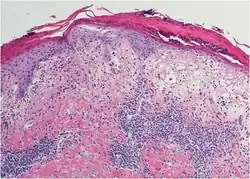

Histopathology

Histopathology show distinct changes in vacuoles and Civatte bodies in all levels of the epidermis.[2] The is melanin incontinence and neutrophils and eosinophils.[2]

Melanin incontinence

Basal vacuolation